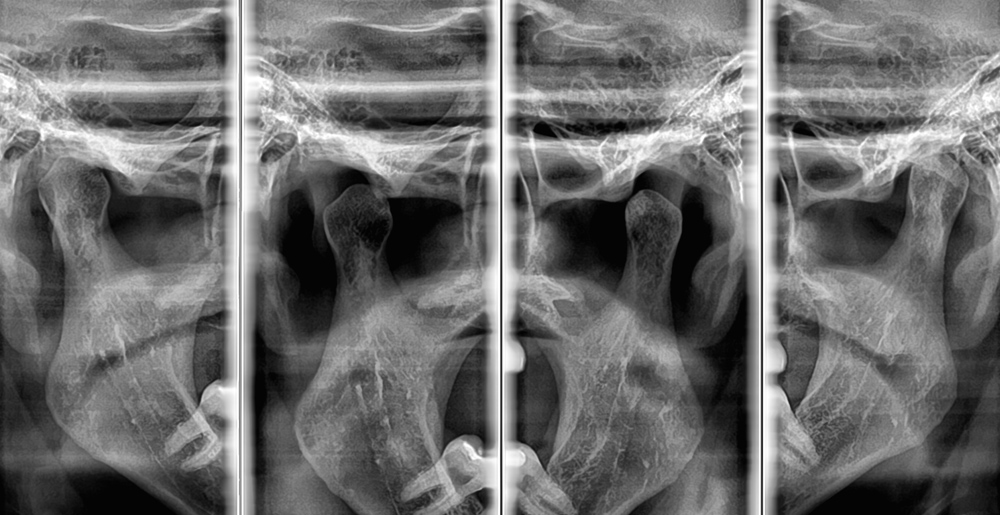

Panorâmica especial para ATM;